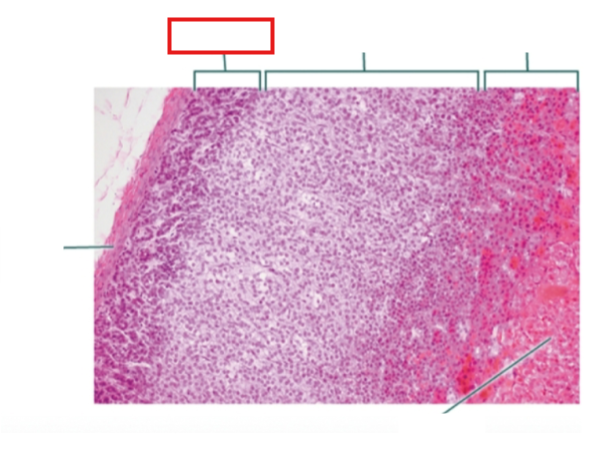

What structure is highlighted?

zona glomerulosa

What structure is highlighted?

zona fasciculata

What structure is highlighted?

zona reticularis

What structure is highlighted?

Capsule

What structure is highlighted?

medulla

What structure is highlighted?

capsule

What structure is highlighted?

zona glomerulosa

What structure is highlighted?

zona fasciculata

What structure is highlighted?

zona reticularis

What structure is highlighted?

adrenal medulla

What tissue is shown?

adrenal gland